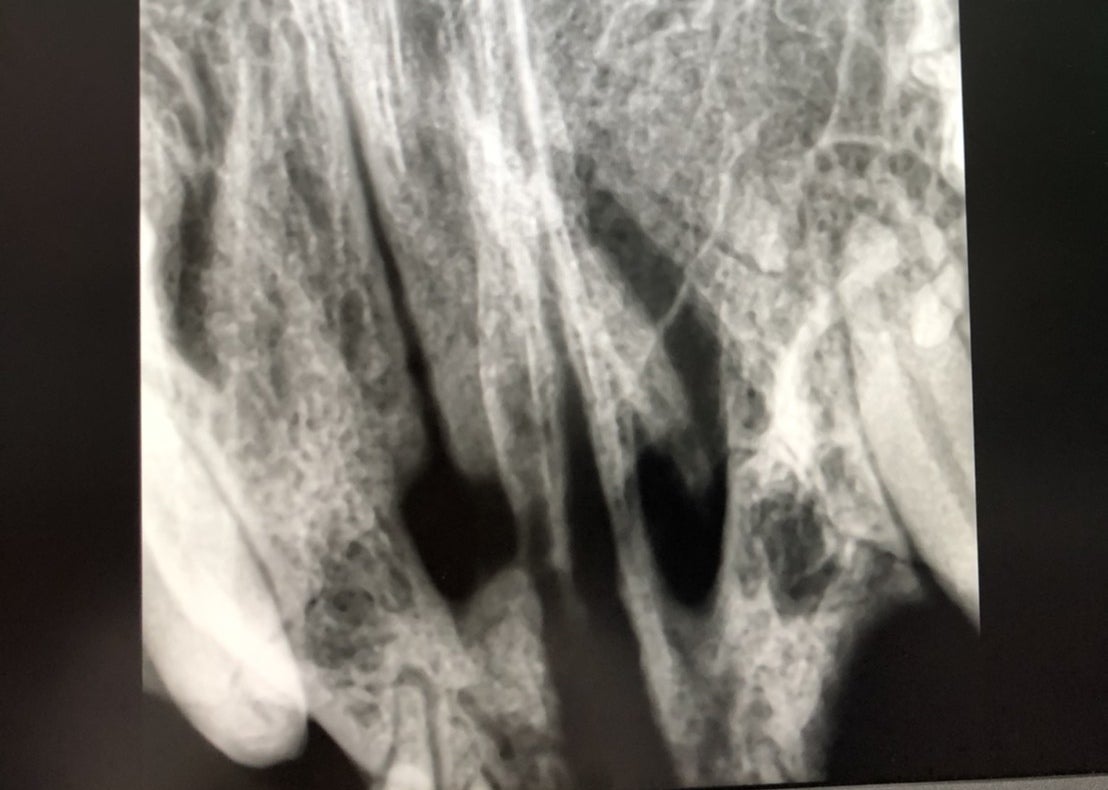

見つけた時の姿はとても酷く、傷口が化膿して顔は膿だらけで鼻からも夥しいほどの膿が流れ出ていました。

保護猫改めニャン吉は必死に生きています。病院の先生にもよく生きていたね、と驚かれた程です。

猫ちゃんの命をただ助けたいと言う思いだけで保護をしました。病院で30万位かかりますが、どうしますか?と言われましたが助ける以外の道はありません。